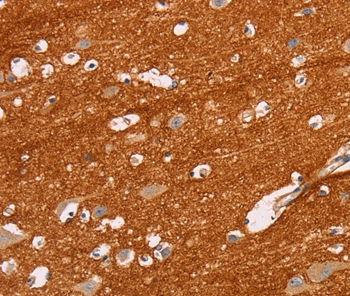

分类: 科研抗体货号: P42783别名: R-PTP-kappa应用: WB,IHC反应种属: Human,Mouse